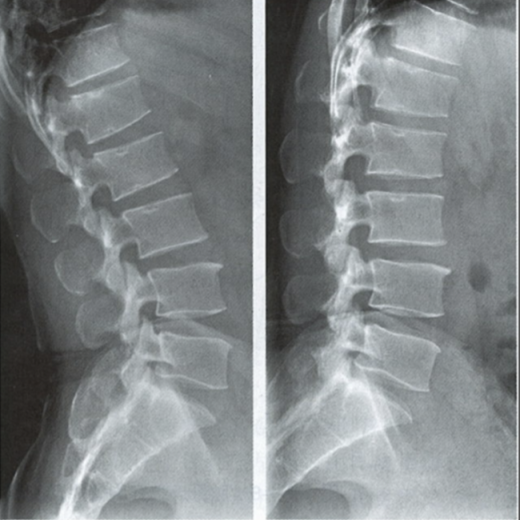

腰椎動力位,也稱為過屈過伸位,可以理解為兩個極限體位下的側(cè)位片,腰椎動力位通過做最大程度彎腰(過屈)和后仰(過伸)的動作拍攝側(cè)位片,來觀察腰椎在極限活動下的表現(xiàn)。如果說腰椎側(cè)位片能靜態(tài)體現(xiàn)椎體的解剖學(xué)結(jié)構(gòu)、序列及生理曲度改變,那么腰椎動力位則是評估腰椎動態(tài)功能性的檢查。

腰椎過伸位:是指腰部盡可能向后伸展,以雙髖關(guān)節(jié)位支撐點,運動前后骨盆位置無改變。腰椎過伸時,向前的曲度大于生理曲度,上部向后傾斜。

腰椎過屈位:是指腰部盡可能向前彎曲,以雙側(cè)髖關(guān)節(jié)位支撐點,運動前后骨盆位置無改變。腰椎過屈的表現(xiàn)位向前的曲度減小、變直,上部向前傾斜。

當1度及以上的滑脫時才可以在普通腰椎側(cè)位上觀察到,而1度以下的滑脫或失穩(wěn)則在普通側(cè)位片上難以發(fā)現(xiàn),這時候就需要借助腰椎動力位進行診斷。

腰椎動力位 左圖為過伸位、右圖為過屈位